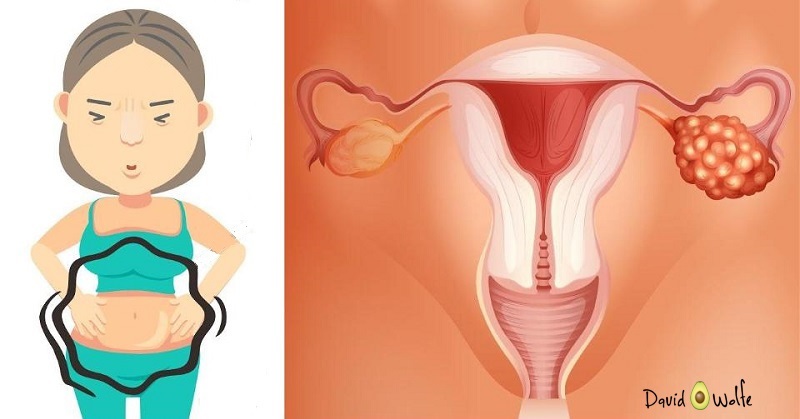

Ung thư buồng trứng là một trong những nguyên nhân gây ra tỷ lệ tử vong đứng thứ 4 trong các bệnh lý ung thư ở nữ giới. Bệnh để lại những hậu quả nặng nề ảnh hưởng đến sức khỏe của phụ nữ, đặc biệt nguy cơ tử vong rất cao nếu như phát […]